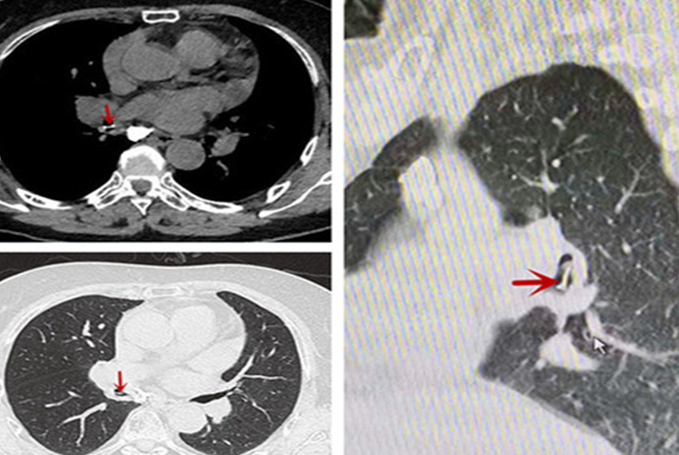

该院呼吸内科主任医师邓新宇接诊后,看了患者的肺部CT片子:“您可能是气管里有异物,建议先做一个气管镜检查”。

随后,经由呼吸内科李树奇副主任医师在全麻下为林大妈行无痛气管镜手术,全程仅5分钟,取出近5厘米的鸡骨头……